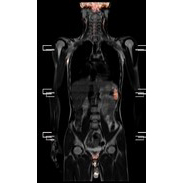

PET-CT検査